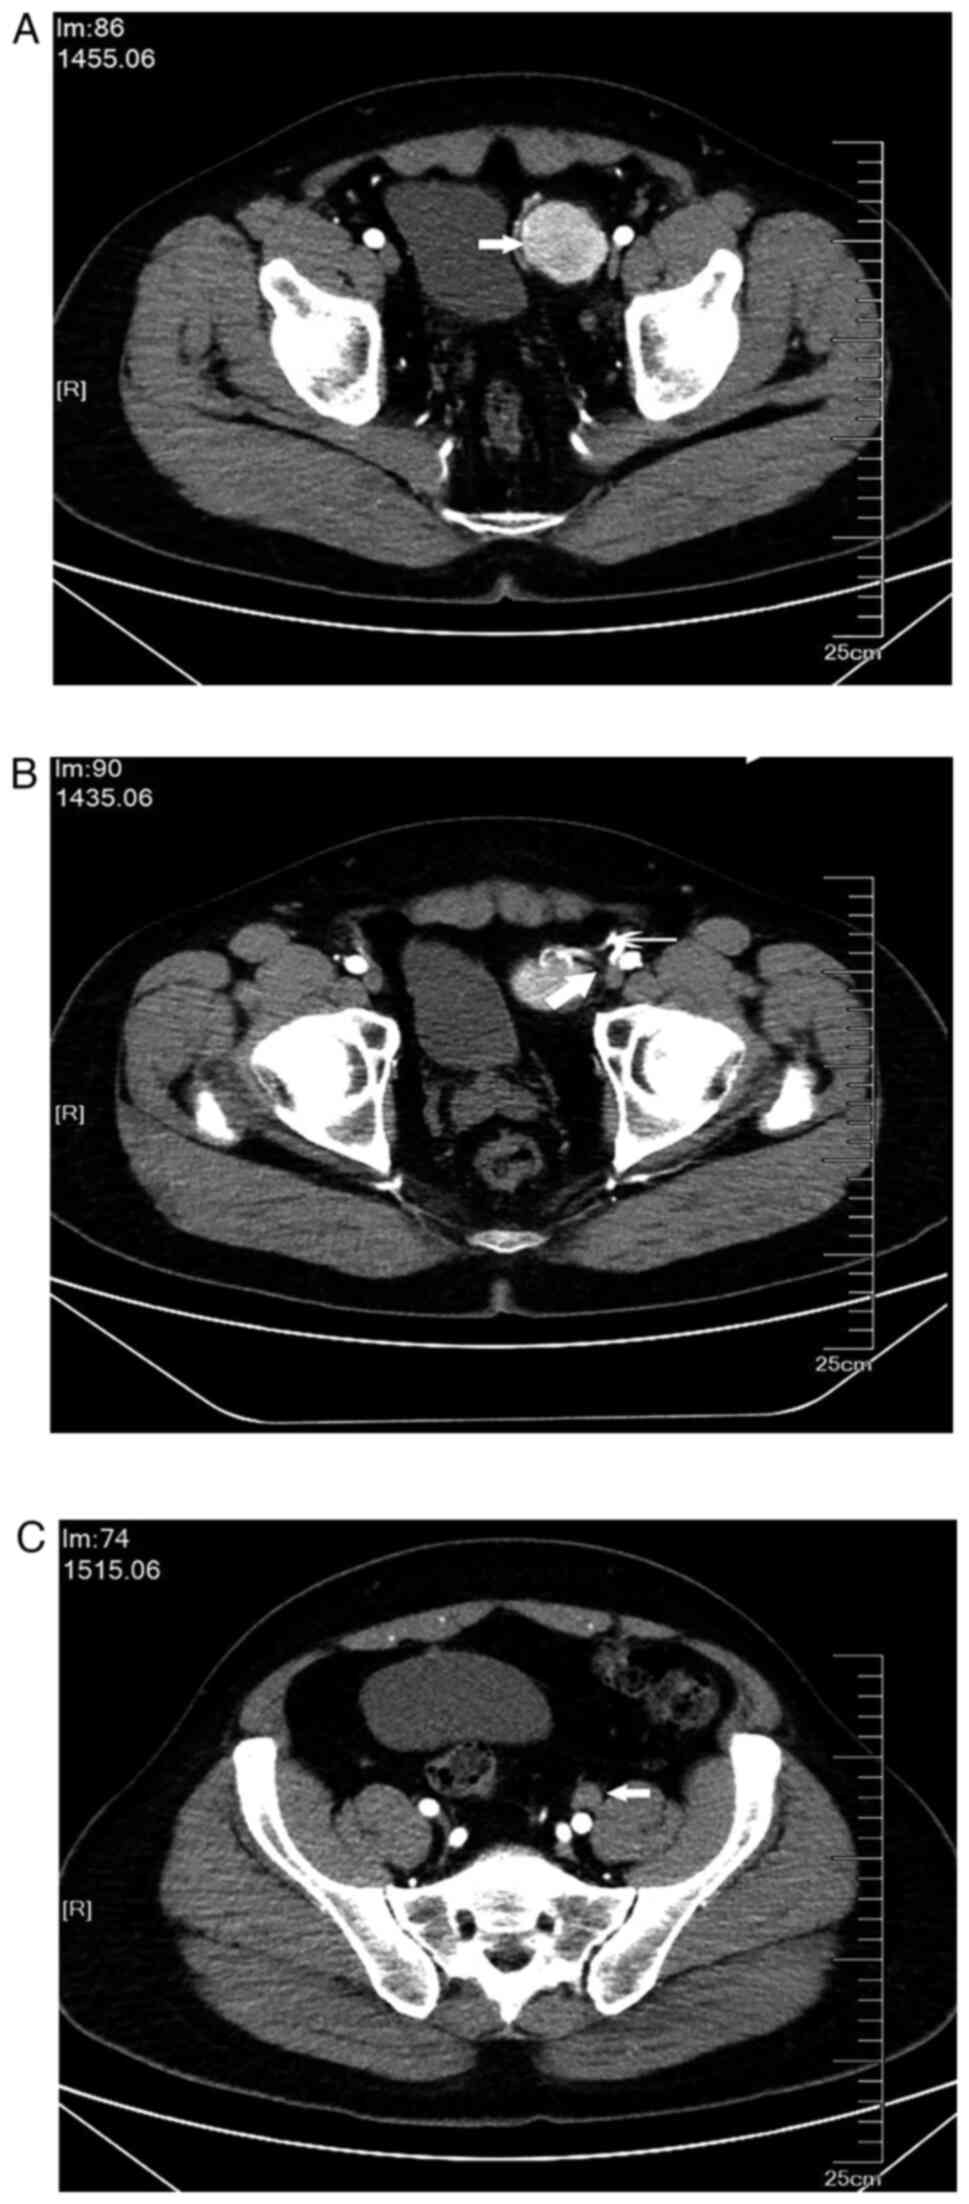

A 38-year-old male patient was referred to The First Affiliated Hospital of Shandong First Medical University and Shandong Provincial Qianfoshan Hospital (Jinan, China) in April 2021 due to a retroperitoneal tumor found in the left side of the pelvis without any symptoms. The patient had no previous illnesses or family history. No enlarged lymph nodes were palpated in the cervical, clavicular or inguinal zones. Laboratory parameters were all normal. Preoperative CT scans of the chest, abdomen and pelvis revealed a retroperitoneal tumor on the left of the bladder measuring 42x38 mm, with a marked contrast effect (Fig. 1A). The arterial supply to the tumor arose from branches of the left external iliac artery, with venous drainage entering the left external iliac vein (Fig. 1B). An enlarged lymph node (21x18 mm) was also detected lateral to the left external iliac artery with no enhancement on CT imaging (Fig. 1C).

Figure 1

Preoperative CT scan of the pelvis. (A) Retroperitoneal tumor located on the left of the bladder with a remarkable contrast effect (arrow). (B) Arterial supply to the tumor arose from branches of the left external iliac artery (thin arrow), with venous drainage entering the left external iliac vein (thick arrow). (C) An enlarged lymph node was located lateral to the left external iliac artery (arrow).